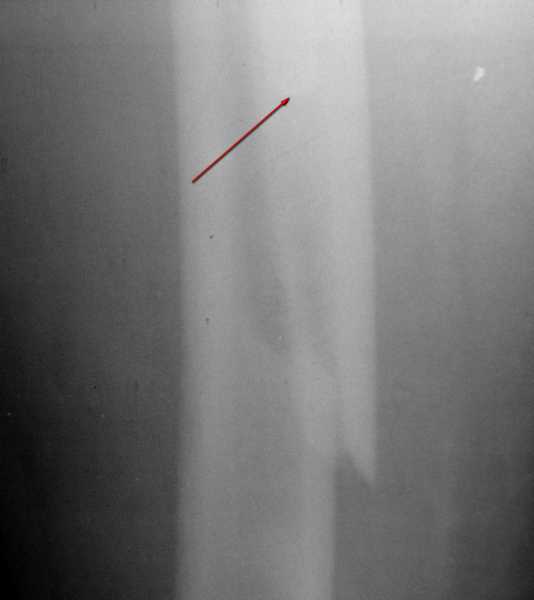

Вот фрагменты этих снимков с более различимыми областями интереса.

Там видно расхождение фрагментов, диастаз чуть медиальнее б. вертела.

Кончик ножки виден на самом верху этого снимка.